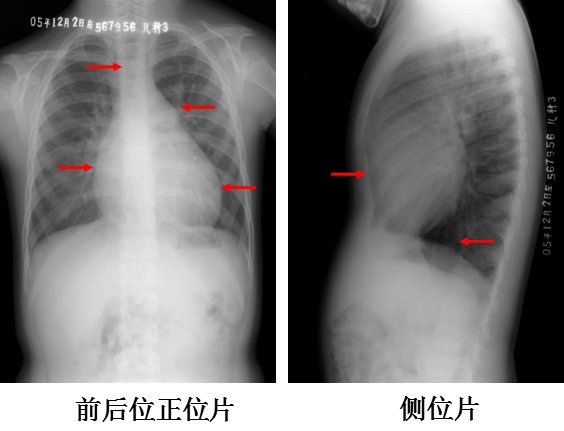

房间隔缺损:胸片表现

△ 肺血增多

△ 心胸比例增大:> 0.55

△ 右房、右室增大

△ 左室小

△ 肺动脉段突出

△ 主动脉结小